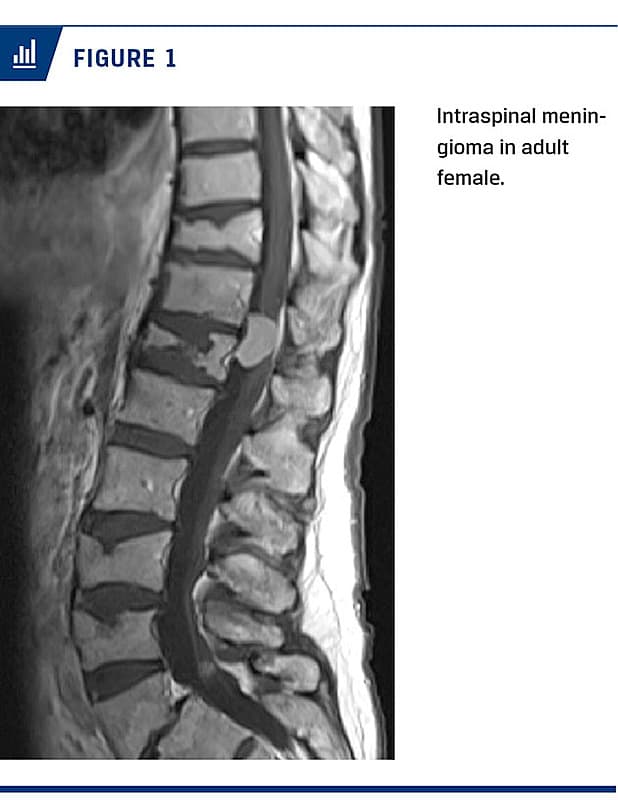

intradural extramedullary tumours and one third were intramedullary tumours. This is in line with the literature, where intradural extramedullary tumours are described in 70-80% and extradural in 20-30% of cases [12]. Schwannoma and meningioma (Figure 1) are the most common among the intradural extramedullary tumours, whereas ependymoma and astrocytoma are the most common among intramedullary tumours. Similar findings were previously reported in the literature [4-7, 12, 13]. We found only three cases with intramedullary astrocytoma, which is less common than reported in the literature [12]. Malignant tumours of WHO grade III or IV are rare [6, 12]. In total, in our study, 7% of all PIST were malignant. The incidence of malignant PIST was found to be similar to that reported in other published studies [6, 14].